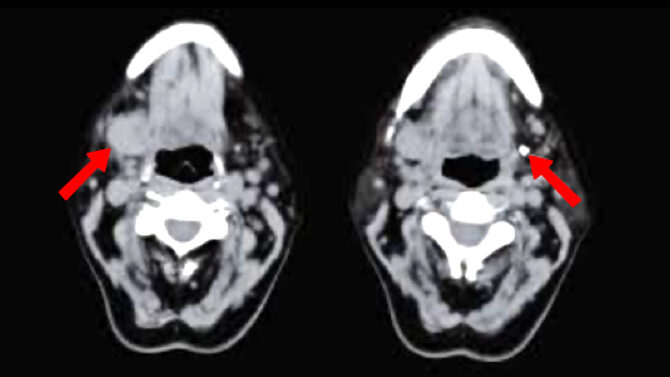

Επιπολής και ολική παρωτιδεκτομή

Σε μια παρωτιδεκτομή, ο παρωτιδικός αδένας αφαιρείται εν μέρει ή πλήρως. Ο λόγος για αυτό μπορεί να είναι χρόνια φλεγμονή ή όγκος. Ο παρωτιδικός αδένας είναι ο μεγαλύτερος από τους σιελογόνους αδένες. Βρίσκεται μπροστά από το εξωτερικό αυτί και εκτείνεται μέχρι τη γωνία της γνάθου. Περιβάλλεται από την παρωτιδική περιτονία, έναν σάκο συνδετικού ιστού. Η…